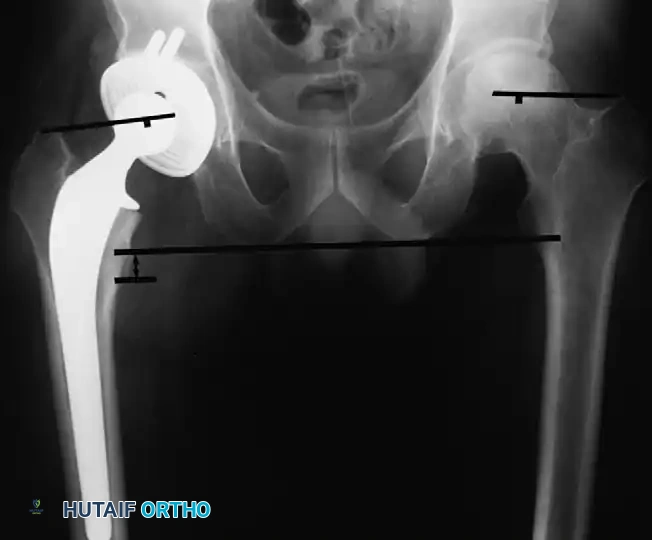

Calcification can typically be visualized radiographically by the third or fourth postoperative week; however, the ectopic bone does not mature fully for 1 to 2 years. The classification system developed by Brooker et al. remains the gold standard for describing the extent of bone formation:

- Grade I: Islands of bone within the soft tissues.

- Grade II: Bone spurs originating from the proximal femur or pelvis with at least 1 cm of space between opposing bone surfaces.

- Grade III: Bone spurs originating from the proximal femur or pelvis with less than 1 cm of space between opposing bone surfaces.

- Grade IV: Complete radiographic bony ankylosis.

The overall prevalence of this complication averages approximately 10% in modern series, though historical data by Riegler and Harris reported occurrences in up to 50% of patients. Fortunately, most patients who develop HO remain asymptomatic. However, restricted range of motion and pain are common in patients with severe Brooker Grade III or Grade IV ossification. Significant loss of function has been reported in up to 10% of affected patients.